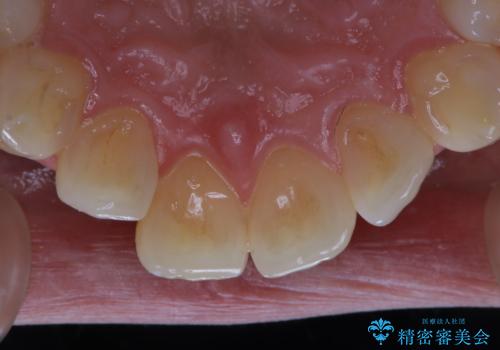

またPMTCを行うことで、ご自身本来の歯の色になり自然な明るさになります。

口元が自然な明るさになることで、より清潔感のある印象になるため結婚式・行事やイベント前などにもPMTCを行うはおすすめです。

ホワイトニングは、歯を削ったり、傷つけたりすることなく歯の内部の象牙質まで浸透し、色素を分解して漂白することで、くすることができます。